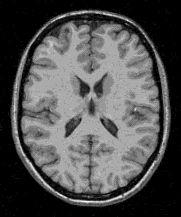

A result example:

classification (grey=100,white=200)